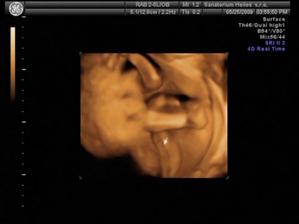

20.1.2009 - těhu potvrzeno od Dr. Máme první fotečku našeho "Prdýska"